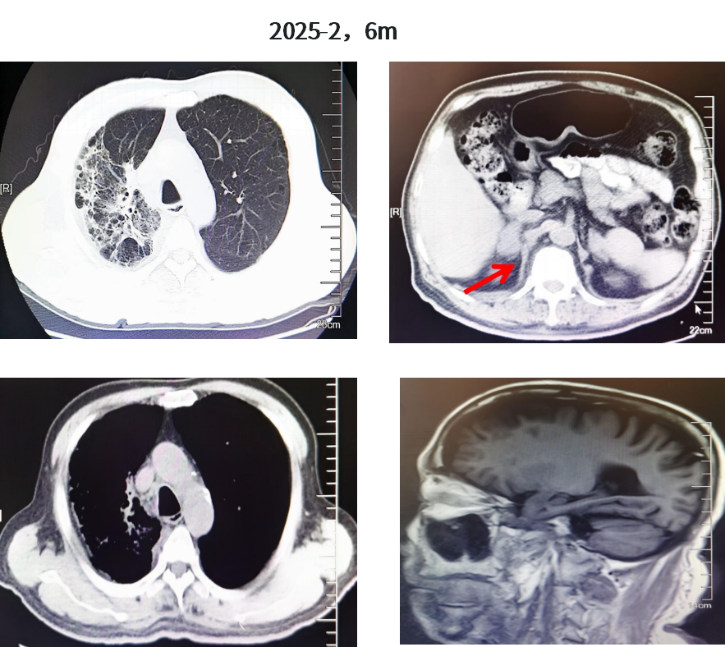

行靶向药物剂量调整:2024年12月-2025年2月一线伏美替尼80mg QD联合伯瑞替尼100mg QD(必要时隔天一次)靶向治疗,并对症治疗:氨溴索+乙磺酸尼达尼布+乙酰半胱氨酸;增强检查改为平扫,加强水化、利尿,使用尿毒清颗粒治疗。疗效整体维持PR,颅内维持CR;但肿瘤标志物较前增高(CYFRA21-1由3.11升至4.44,CA19-9由23.65升至107.7)。2025年2月复查双侧肾上腺转移瘤较前略增大变饱满(右侧长径42mm,左侧长径38mm),提示疾病进展(PD)趋势,未达PD标准。

图5.胸部CT、肾上腺CT及颅脑MR结果(2025.02)

靶向药物建议调整为一线伏美替尼80mg QD 联合伯瑞替尼100mg BID 靶向治疗(伯瑞替尼建议QD增加为BID);但患者高龄,且未出现肾上腺进展后的不良反应,仍自行继续伏美替尼80mg QD+伯瑞替尼100mg QD口服靶向治疗。2025年4月,肿瘤标志物继续增高(CYFRA21-1升至6.89,CA19-9升至293.6)。